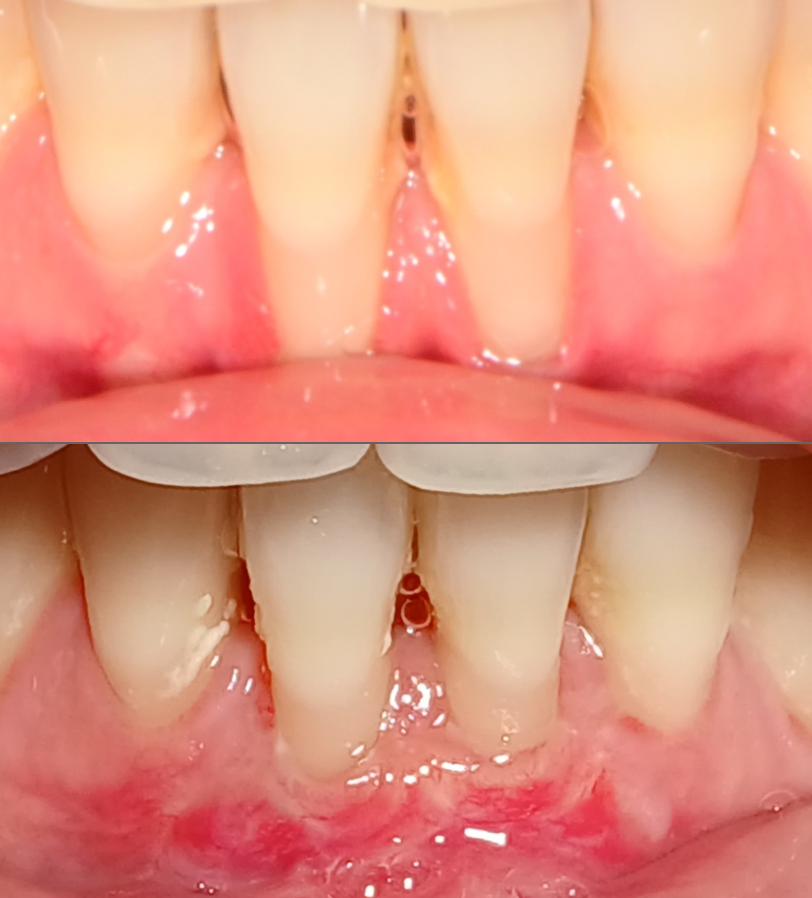

잘못된 교정치료로 잇몸퇴축이 발생할 수 있습니다.

상환에 맞게 잇몸이식이 필요할 수 있습니다.

위 사진은 수술 후 3주 지난 모습입니다.